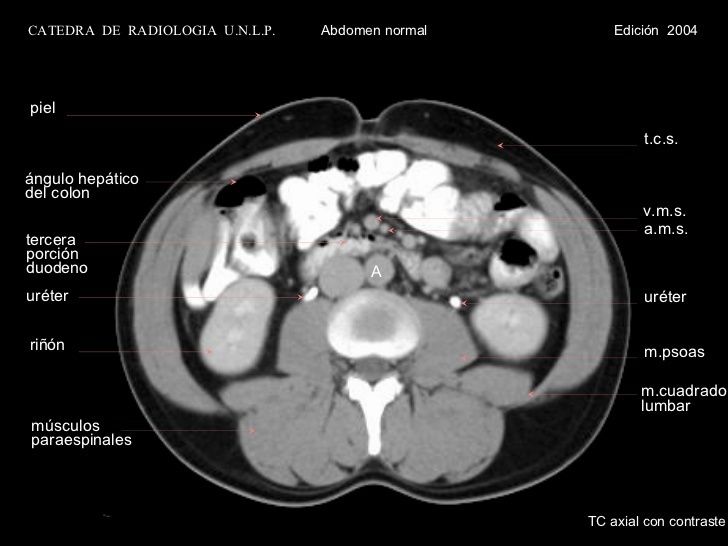

TC DE ABDOMEN Y PELVIS

Es una radiografia tomada de manera continua. Entrega detalle antaomico muy superior a la radiografia simple. Permite evaluar lesiones menores de 1 mm. El problema es que se irradia al paciente y se usa medio de contraste que úede afectar a la funcion renal. Pielo TC: No usa medio de contraste. Para ver litiasis especificamente, menos de 700 unidades de desnisas son calculos radiolucidos como los de acido urico. Permite determinar carga litiasica, localizacion , densidad, signos secundarios( inflamacion, dilatacion. compromiso pre renal) y el pronostico TC de abdomen y pelvis siempre es con contraste y permite determinar carga litiasica, progrmar citugia, evaluar que via utilizar. Permite caracterizar masa renales, suprarrenales, infecciones de tracto urinario como PN complicada, hidropionefrosis, absceso renal, absceso perinefritico, alteraciones anatomicas de via urinaria superior, etapificacion de neoplasia riñon y suprarrenales, trauma urnario El hueso se ve blanco y el aire o agua se ve negro. Se evlua a traves de densidad tomografica de Hounsfield

Uro TC:  Tiene una fase sin contraste como el pieloTC, fase corticomedular que dura 40 minutos, donde se ven lesiones del parenquima y se ven bien definidos los riñones, luego la afase nefrogenica donde se impregana las masas renales y por ultimo la fase tardia o excretora, donde se ve bien dibujado el sistema urinario. Sirve para ver lesiones de urotelio que midan menos de 5 mm. En estudio de hematurio se utiliza cistografia y Uro TC. Lesiones de urotelio superior, rotura de via excretora, lesiones de vejiga.